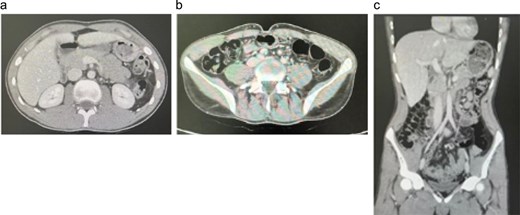

Following multidisciplinary team discussion, the patient was managed medically with voriconazole, administered at 400 mg every 12 h for one day, then 200 mg every 12 h for a total of 6 months. He tolerated therapy well, with complete resolution of abdominal pain and no new gastrointestinal symptoms. A follow-up contrast-enhanced computerized tomography scan (Fig. 2) showed a dramatic reduction in the size of the hepatic lesions and resolution of cecal wall thickening, indicating a marked radiologic and clinical response to antifungal treatment.

Follow-up contrast-enhanced CT abdomen in Case 1. (a) Axial image through the upper abdomen showing interval disappearance of the previously described hepatic lesions. (b) Axial image at the level of the right iliac fossa demonstrating resolution of cecal/right colonic wall thickening and surrounding inflammatory changes. (c) Coronal reformatted image confirming normalization of right colon and liver appearance, consistent with an excellent radiologic response to prolonged voriconazole therapy.